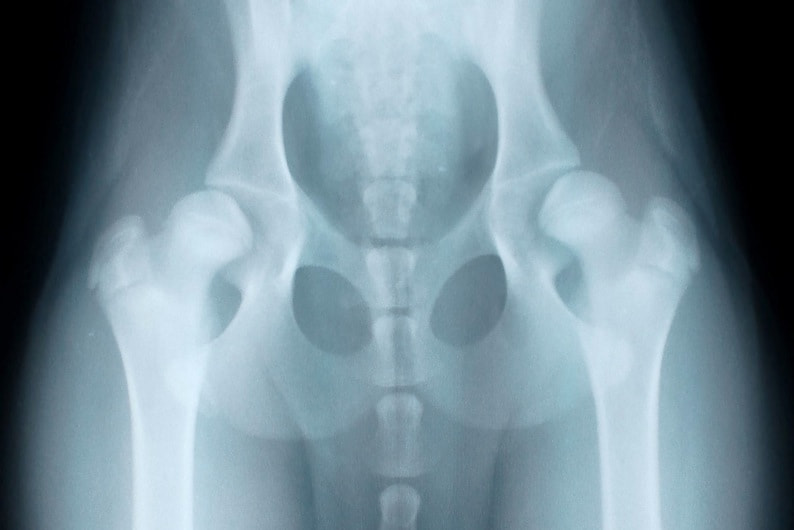

右は股関節伸展像(OFA法)、左は伸延ストレス撮影像で、両者は同じ患者のレントゲン写真です。股関節伸展像(OFA法)では大きな異常は認められませんが、伸延ストレス撮影像では寛骨臼と大腿骨頭の距離が広く、股関節の緩みが認められます。